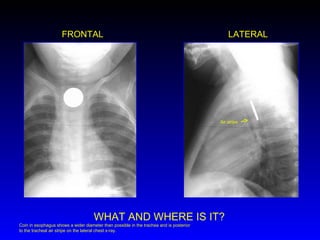

FRONTAL LATERAL WHAT AND WHERE IS IT? Air stripe Coin in esophagus shows a wider diameter than possible in the trachea and is posterior to the tracheal air stripe on the lateral chest x-ray.

• #79 Coin in esophagus shows a wider diameter than possible in the trachea and is posterior to the tracheal air stripe on the lateral chest x-ray.